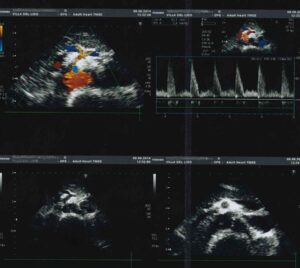

L’esame ecografico dell’aorta addominale ha principalmente lo scopo di identificare per tempo la dilatazione ( aneurisma ) di questa grossa arteria. L’esame consiste nell’appoggiare una sonda ecografica sull’addome, da sotto lo sterno fino all’ombelico, e nella registrazione delle immagini e dei grafici doppler.

L’esame semplice e privo di radiazioni serve pertanto ad individuare tale patologia, seguirla nel tempo e, quando necessario, porre l’indicazione ad un intervento chirurgico ( aneurismectomia ). Con la metodica in oggetto, in casi selezionati, si può anche verificare la possibilità di un’intervento mediante applicazione di endoprotesi.